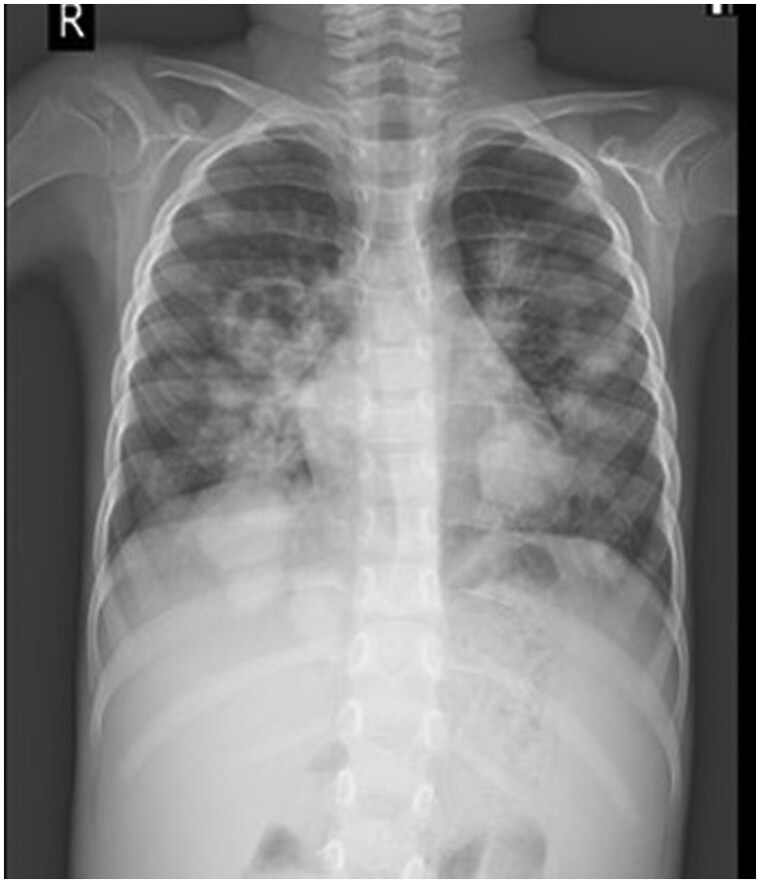

Bronchocentric granulomatosis is a rare form of granulomatous disease characterized by peribronchiolar or peribronchial necrotizing granulomas.1 The imaging findings are non-specific and include nodular or mass-like lesions and pneumonic consolidation.2 We present a case of bronchocentric granulomatosis in a patient with Pre-B-cell acute lymphoblastic leukaemia. The aim of the case report is to make the radiologist aware of this condition and emphasize the importance of multimodality approach which along with clinical findings helps in reaching a diagnosis and managing this rare complication.